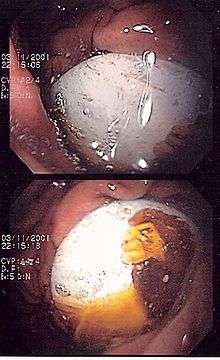

One death and four serious injuries led to the recall of 3.8 million Magnetix building sets in March 2006. The magnets inside the plastic building pieces could fall out and be swallowed or aspirated.[36] In 2009, Avolio L and Martucciello G published on The New England Journal of Medicine the effects of magnetic toys ingestion in two children ("Ingested Magnets".Luigi Avolio, M.D., and Giuseppe Martucciello, M.D. N Engl J Med 2009; 360:2770June 25, 2009) Since then MEGA Brands has implemented design enhancements to Magnetix, including sonic welding of panels, 100% inspection, gluing magnets into rods, elimination of 3+ labeling in favor of 6+ labeling after it assumed operational control of Rose Art on 1 January 2006. Only safe and improved products are currently on store shelves.[37]